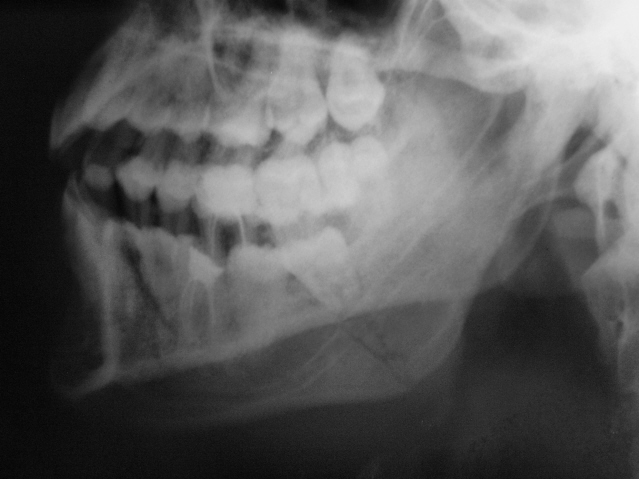

Вот один из них.

Валентин Львович! Результат налицо. Открытый перелом в области 8-го зуба. И на противоположной стороне в области 2-3-го зубов.

Переломы: через лунку 8 с одной стороны, с другой - в обл 3/4.

Замечания: не маркирована сторона, не достаточно косой снимок - наложение сторон. Стоило снять с двух сторон.